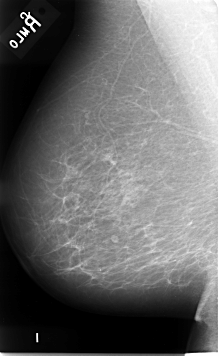

B_3086_1.LEFT_MLO

LEFT_MLO LINES 4616 PIXELS_PER_LINE 2832 BITS_PER_PIXEL 12 RESOLUTION 50 OVERLAY

FILE: B_3086_1.LEFT_CC.OVERLAY

TOTAL_ABNORMALITIES 1

ABNORMALITY 1

LESION_TYPE MASS SHAPE OVAL MARGINS ILL_DEFINED

ASSESSMENT 3

SUBTLETY 3

PATHOLOGY MALIGNANT

TOTAL_OUTLINES 1

BOUNDARY